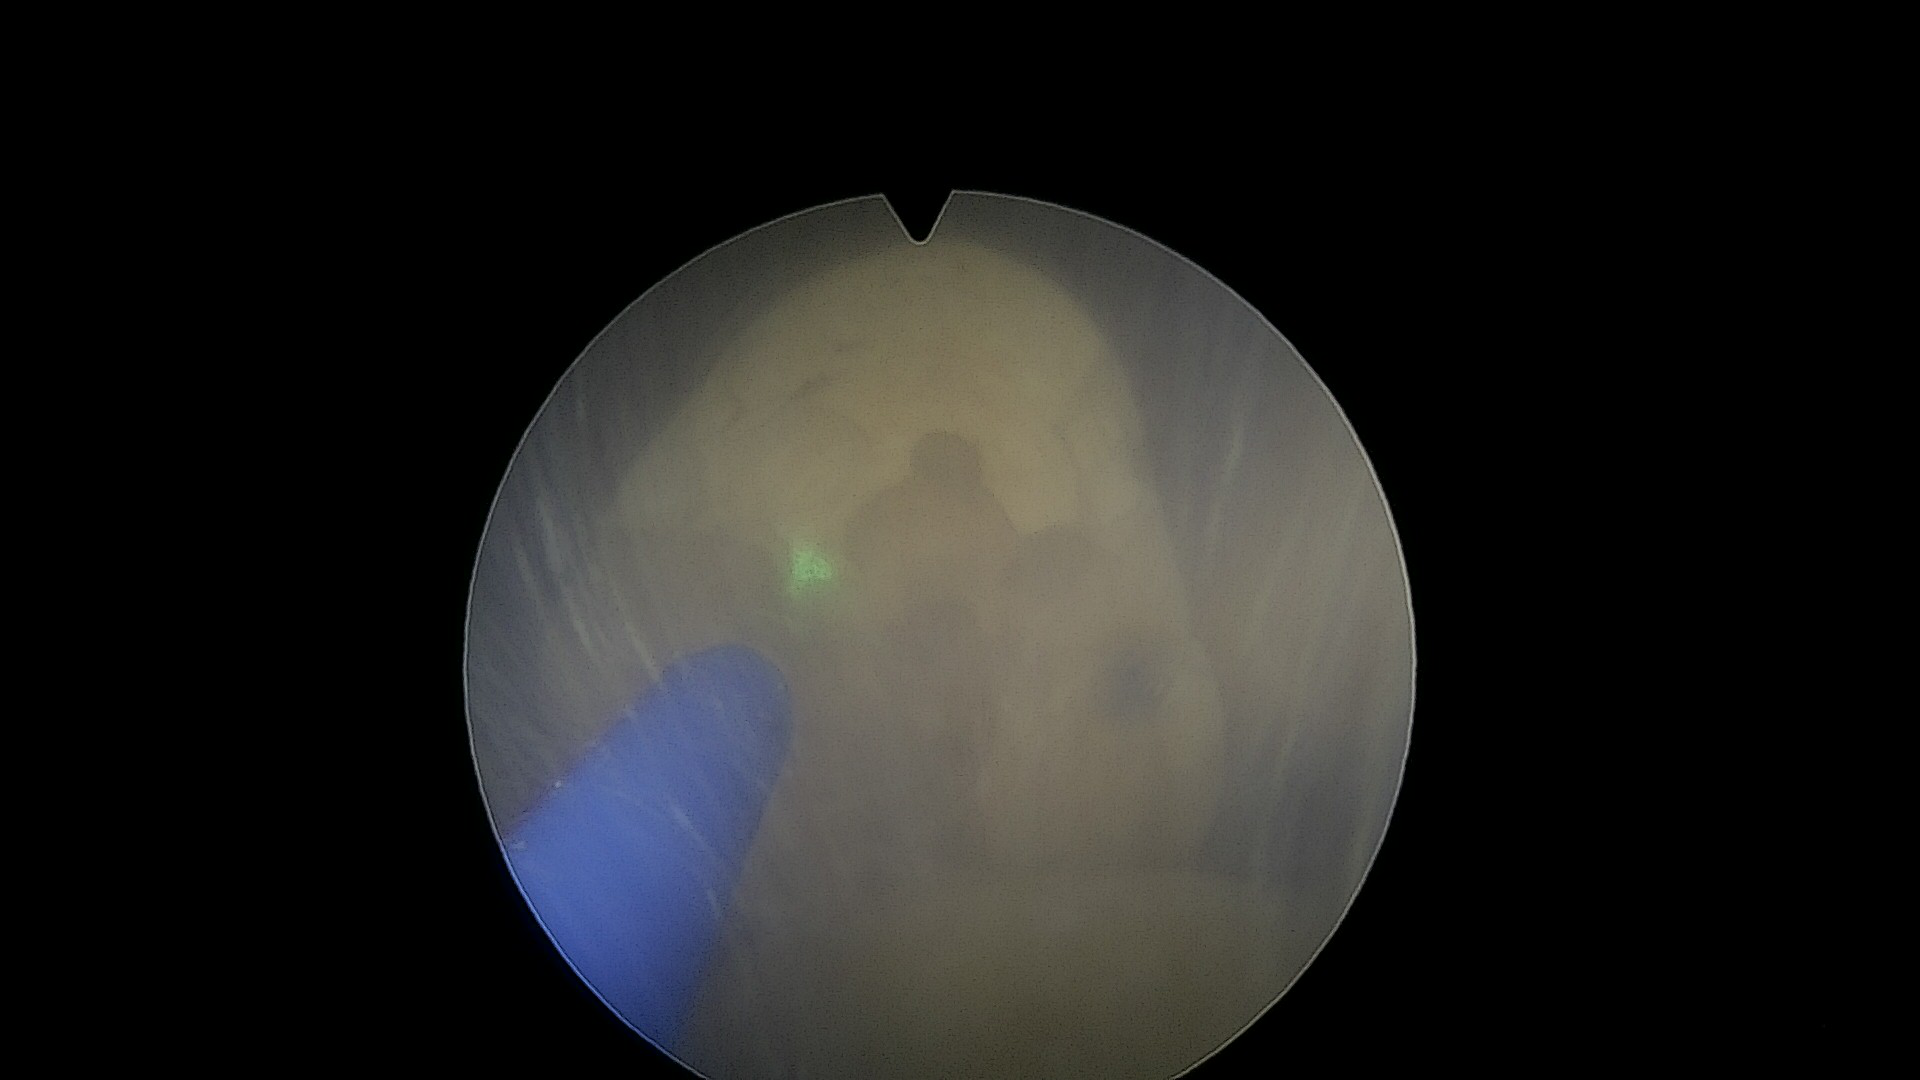

3.钬激光碎石系统

泌尿系统结石的钬激光碎石